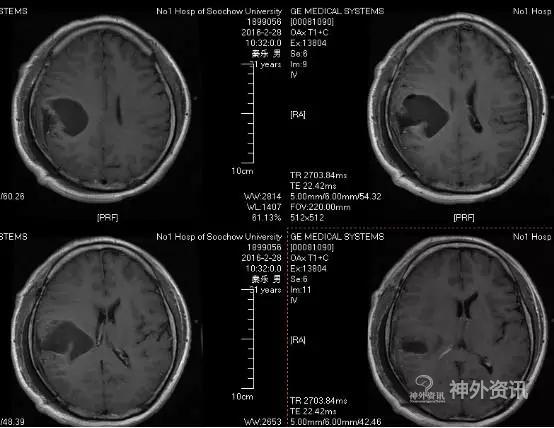

头颅MR示:右颞顶囊性占位伴结节,考虑胶质瘤可能。MRI T1为等信号(图1);T2囊液为高信号(图2);结节为均匀增强(图3);弥散相显示弥散受限(图4)。

图3. 结节为均匀增强。

术后患者恢复良好,神志清,精神佳,四肢肌力V级,肌张力正常,病理征(-)。术后CT(图5)MRI(图6)未见血肿,肿瘤全切。

图5. 术后2小时CT。

图6. 术后48 小时 MRI (增强)。

PXA在CT平扫时表现为低密度囊性病变,境界多较清楚;附壁结节呈稍低密度或等密度,壁结节常紧邻软脑膜;囊性区因含有蛋白或出血,在CT上为略高于脑脊液的液性密度。在MRI上T1W1囊性区呈低信号,壁结节为低或等信号,T2W1为囊性区呈高信号,壁结节为稍高信号。增强扫描可见肿瘤附壁结节明显强化,囊壁可轻度强化或不强化,囊壁强化代表囊壁为肿瘤组织,囊壁不强化说明囊壁为反应性增生的胶质细胞构成。影像学典型表现为囊性病变伴壁结节,少数呈囊实性病变,钙化少见。充分认识这些影像特征有助于提高其诊断及鉴别诊断的准确性,为临床治疗及对预后的判断提供重要的参考价值。少数PXA表现不典型,呈囊实性病变,表现为密度或信号不均匀,增强扫描呈不均匀强化。